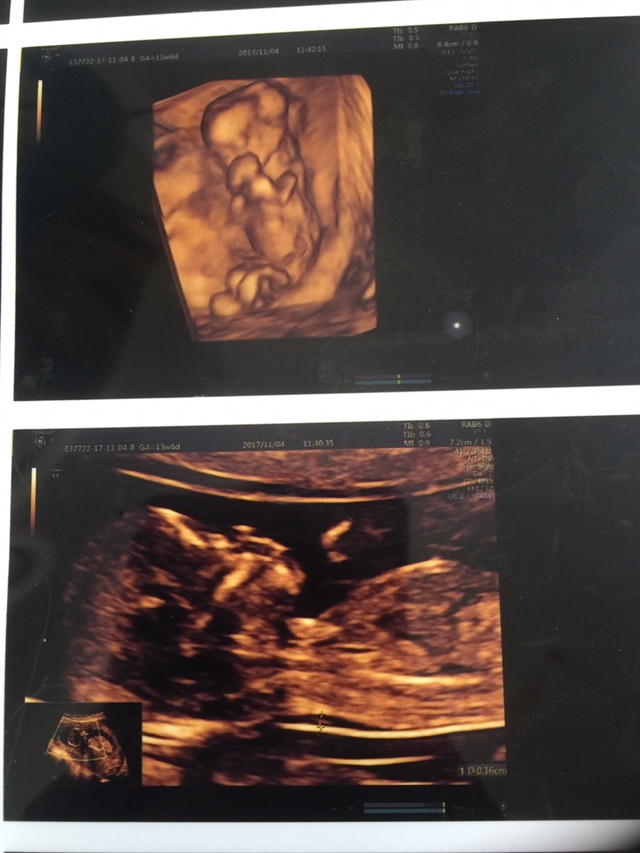

宝宝5个月21天

孕13周+0天

希尔[帖主]:做的很详情 医生还刻了一段动态u盘

希尔[帖主]:做的时候我一直在看它吃手的动态图 一点点小 医生说小了几天